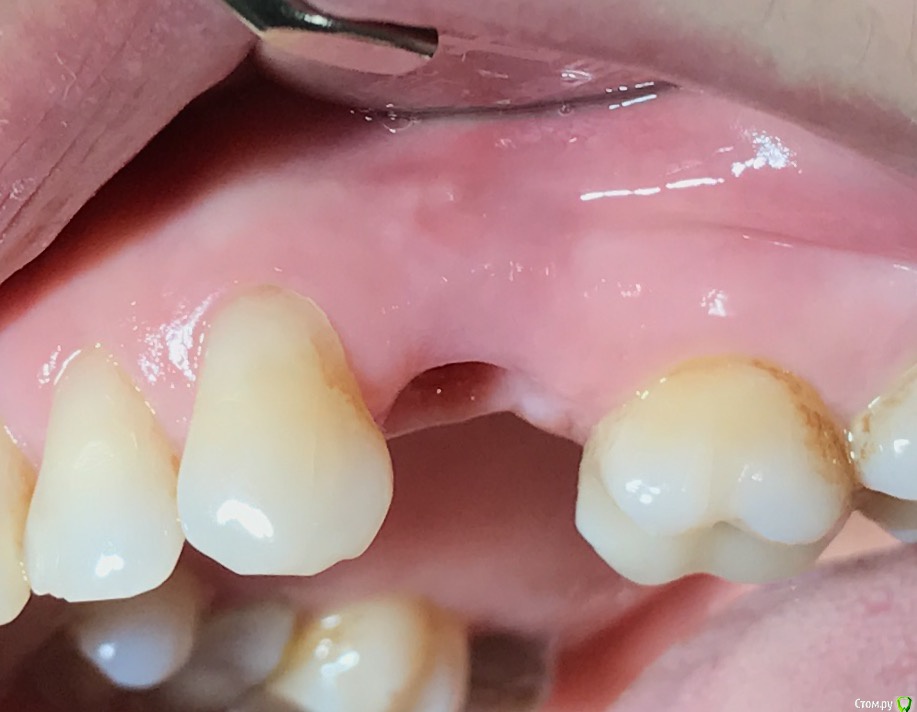

колесников Опубликовано 25 февраля, 2017 Поделиться Опубликовано 25 февраля, 2017 Здравствуйте коллеги! Представляю вашему вниманию этот клинический случай.В ноябре 2016 обратилась пациентка с жалобами на выпадение ортопедической конструкции в обл 24. Объективно: корни 24 не состоятельны. ,на десневом крае в проекции 24 свищевой ход с гнойным отделяемым.На КТ резорбция вестибулярной компактной пластинки и деструкция костной ткани в области щёчного корня.Приняв во внимание крайне негативное отношение пациентки к каким бы то ни было хирургическим вмешательствам и высоким эстетическим требованиям,было решено пойти на немедленную имплантацию .Снимки в день вмешательства,через 7,14 дней и 3мес.Имплант Astra tech profile 4.5х11мм. Сст с бугра вестибулярно. Вместо графта губки Коллапола (не вспомню причину,либо не было в наличии,либо отказ пациента). 15 Ссылка на комментарий

колесников Опубликовано 26 февраля, 2017 Автор Поделиться Опубликовано 26 февраля, 2017 Да,можно было ещё на 1мм притопить,и конечно графт вестибулярно оставить,но это стало понятно только сейчас. При постановке имплант был заглублен на 3 мм, посчитал что этого достаточно, но резорбция случилась больше планируемой. Первоначально планировалась нагрузка через 5 сут ,но ортопед позднее отказался от этой идеи. Думал заменить фдм на зебру,но пациентка пропала на 3 мес... Как получилось,так получилось. Торк был 35н/см,как обычно на астре. Ссылка на комментарий